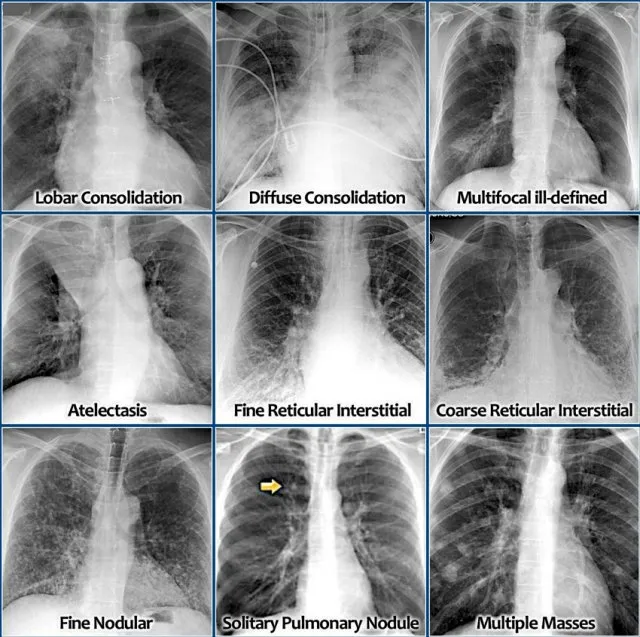

- Chest X-ray: Key to diagnosis. Look for:

- Lobar consolidation: Classic for S. pneumoniae.

- Interstitial infiltrates: Atypical pathogens (e.g., Mycoplasma).

- Cavities: S. aureus, anaerobes, TB.